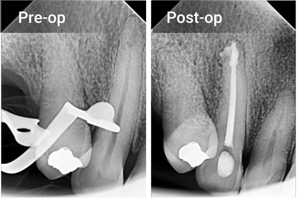

“The canal presented some internal reabsorption. Great results were achieved with this obturation technique and thanks to the great flowability of ZenSeal Pro”

– Dr. Valeria Range1

Excellent Radiopacity

The highly radiopaque and hydrophilic sealer provides tight

adhesion to both dentin and gutta percha points.